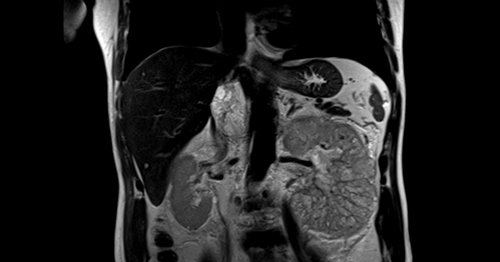

63岁王老伯已退休颐养天年,近期被持续十余天的肉眼可见血尿所困扰,而且常感觉浑身乏力。在当地医院就诊,被诊断为左肾癌,而且肿瘤已经沿着左肾静脉长至下腔静脉,形成了多发癌栓。王老伯辗转省内多家医院就诊,最终转到省立医院泌尿微创二科夏庆华教授团队处。科室完善肾脏强化MR平扫+动态增强检查,显示为左肾恶性肿瘤并下腔静脉癌栓。

术前MRI示左肾恶性肿瘤并下腔静脉癌栓

王老伯所罹患的肾癌是泌尿系统常见的恶性肿瘤,发病率位居第二位,占成人恶性肿瘤的2%-3%。肾癌发展到晚期时肿瘤可能长入肾脏静脉,甚至是更大的下腔静脉,这些长入静脉内的肿瘤就被称为“癌栓”。结合影像学资料,术前诊断为左肾肿瘤并癌栓(cT3cNxMx,梅奥分级III级)。肾癌合并下腔静脉癌栓手术是泌尿外科最复杂手术之一,手术风险巨大,面临手术中大出血、瘤栓脱落导致肺栓塞可能,一旦癌栓脱落游走至肺、心脏导致肺栓塞、心梗,将可能瞬间致命,被誉为是泌尿外科手术中“皇冠上的明珠”。